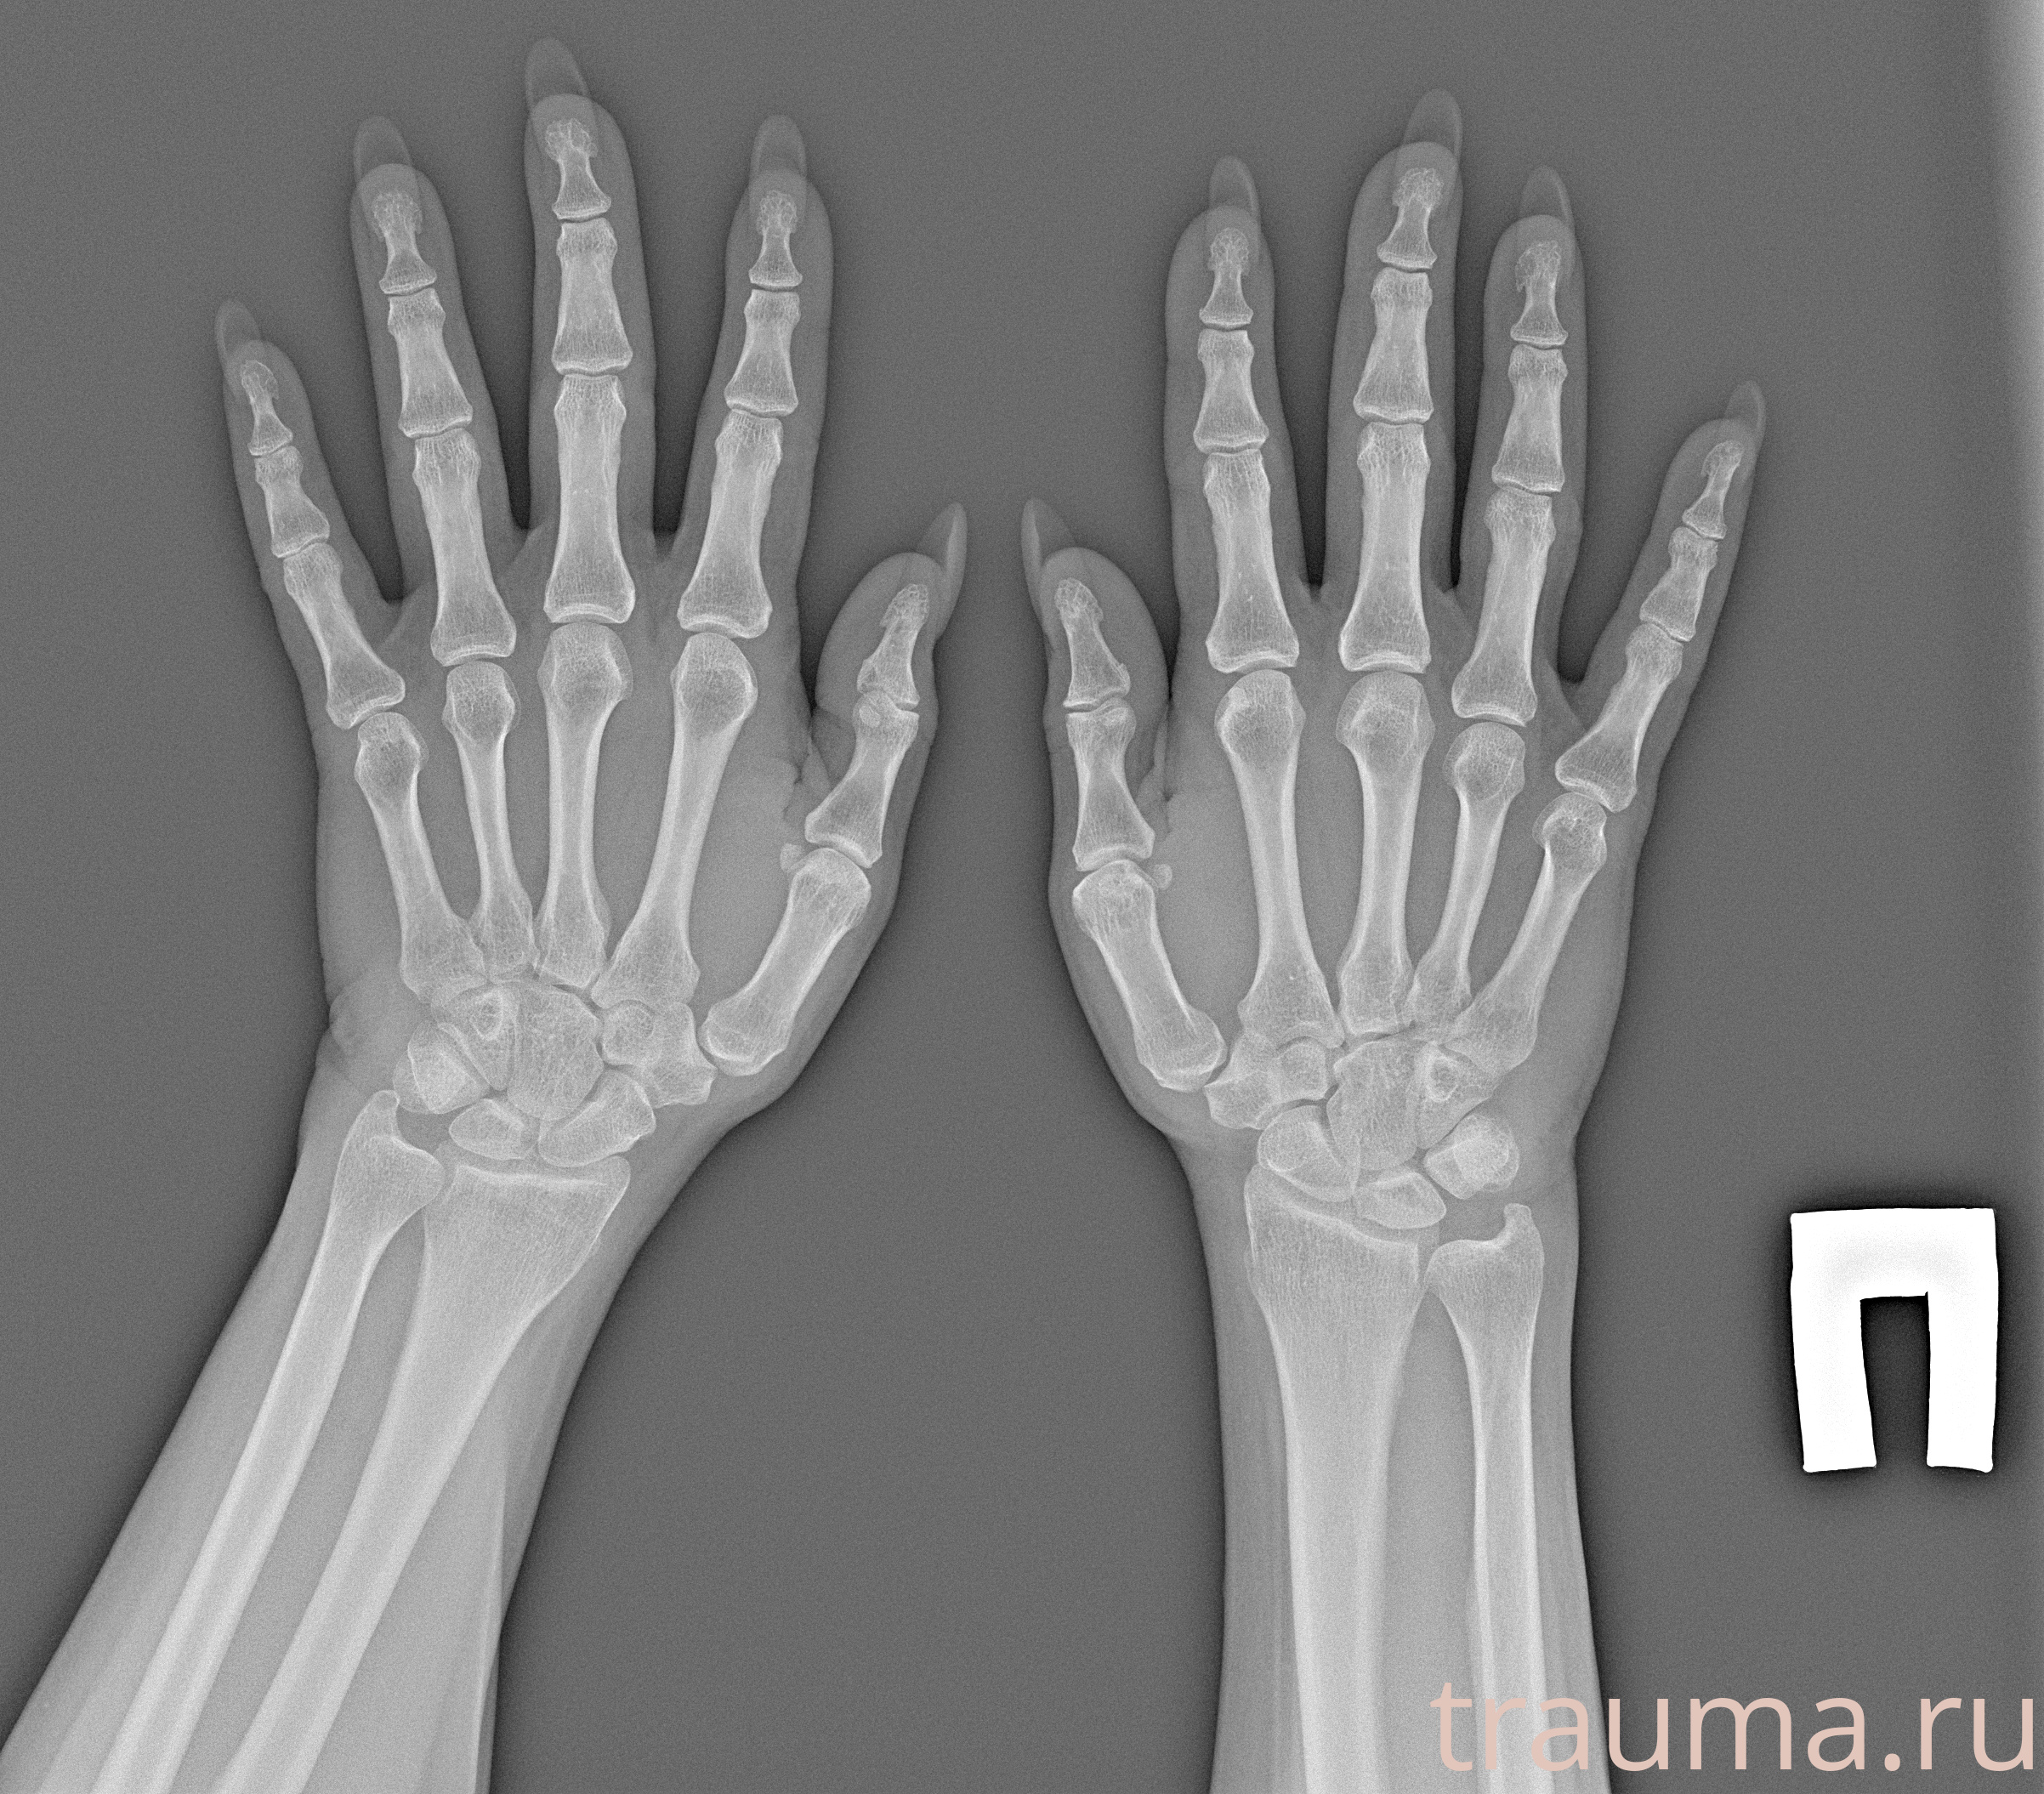

Рентгенограммы

Рентген на дому: по вашему адресу приезжает врач-рентгенолог, травматолог-ортопед с мобильным рентгеновским аппаратом, проводит диагностику травмы или заболевания, делает необходимые рентгенограммы, дает рекомендации по дальнейшему лечению. Получить качественные снимки в домашних условиях возможно благодаря уникальной методике, разработанной МосРентген Центром для института  Склифосовского